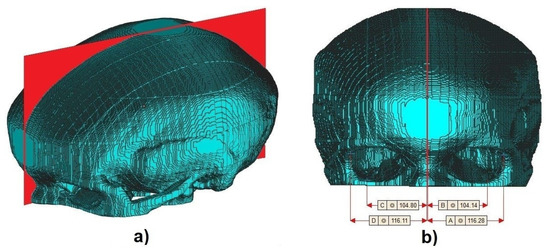

3.3. Geometric Moments Image Center

Finally, to calculate the center of the volumetric images, Equations (8) to (13) were used. As there are no patterns to validate the accuracy of the center-point, visual evaluation was used and compared with cephalometric landmarks. Figure 8 and Figure 9 show the cross-sectional plane created from the geometric moments. Figure 9a presents the perspective view and Figure 9b shows the front view of one aligned sample with measured dimensions of frontozygomatic suture and orbitale in the sagittal plane displayed in Materialise MiniMagic software. We used [28] to convert from voxel into STL file format.

Figure 8.

12 samples with their respective cross-sectional plane created using geometric moments.

Figure 9.

(a) Perspective and (b) front view.